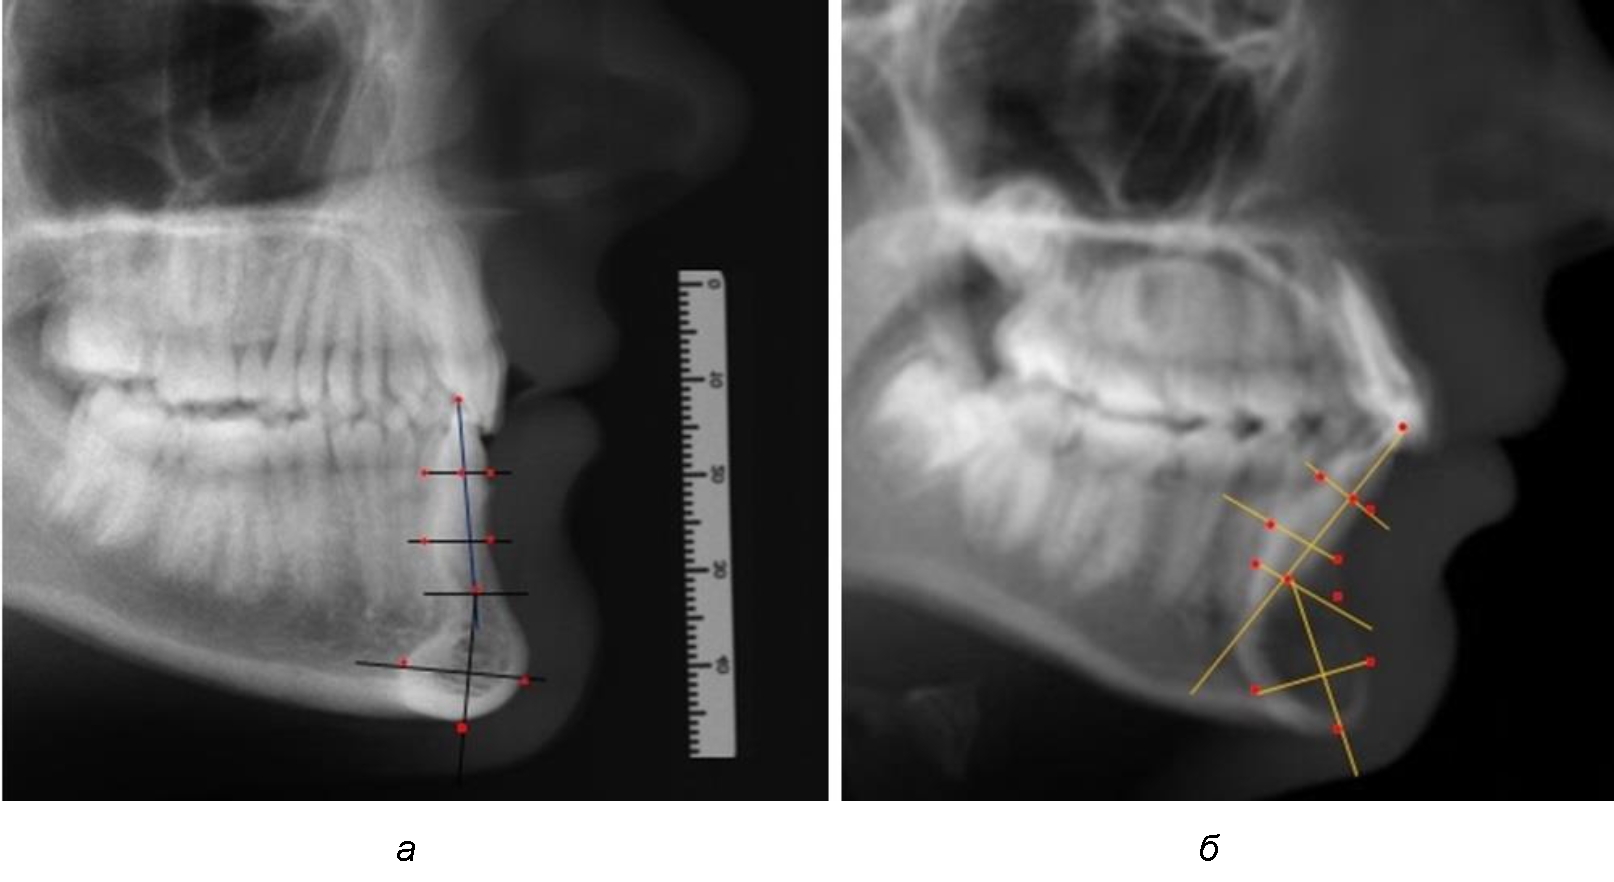

При аномалиях окклюзии в сагиттальном направлении и характерных для них различных вариантах протрузионного и/или ретрузионного патологического положения передних зубов, как правило, сопровождается изменениями параметров подбородочного выступа. Учитывая многообразие форм аномалий окклюзии, параметры подбородочного выступа вариабельны как по сагиттали, так и по трансверсали.

Нередко отмечается деформация подбородочного выступа и различное его положение по отношению к зубоальвеолярной части сегмента. При мезиальной окклюзии нередко нижняя подбородочная точка смещается кзади по отношению к условной срединной вертикали нижнего резца, а при дистальной окклюзии отмечается компенсаторное отклонение подбородка кпереди (рис. 5).

Рис. 5. Особенности нижнечелюстного резцового сегмента на ТРГ у людей при мезиальной (а) и дистальной (б) окклюзии

Кроме того, так же как и у людей с физиологической окклюзией, определялось различие в положении апикальных точек Downs и Schwarz, что, по нашему мнению, может определять тактику лечения патологических форм протрузии/ретрузии резцов с учетом биотипа костной ткани.